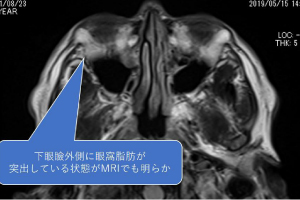

美容外科手術後の修正についてA大学病院の美容外科で皮膚からの脂肪移動術(ハムラ法)したものの改善なく有名な美容外科で結膜から脂肪切除、さらに皮膚切開からの脂肪切除、再度結膜からの脂肪切除、と計4回美容外科での手術を施行された方です。

最後にB美容外科で行った手術では瘢痕のためほんのわずかな量の脂肪(小豆大と言われたそうです)しか切除できなかったとのことでした。どうにか改善したいと悩まれて受診しました。

明らかに大きな脂肪の突出があり、下眼瞼も上眼瞼も膨らんでいました。

この症例の場合、表面の脂肪だけが問題なのではなく、その奥の脂肪も問題なのです。

このためバセドウの方の減圧に準じて眼窩深部の脂肪減圧手術を行いました。

今までに数回の手術を繰り返していますので入り口は瘢痕でガチガチでしたが、思った通りその後ろ(眼窩深部)の脂肪は操作されていませんでしたので比較的簡単に切除することが出来ました。

術前後の写真を提示いたします。